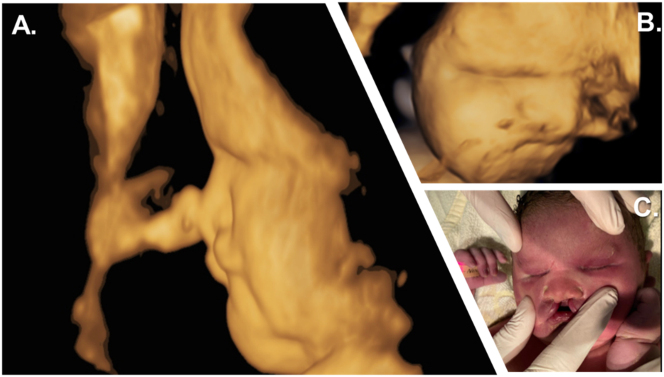

Case presentation: Here, we present a child's case diagnosed with bilateral anophthalmia at 33 weeks of gestation. The newborn was delivered vaginally with a RAX-gene-linked syndrome. Besides craniofacial malformations (bilateral anophthalmia, craniofacial hypoplasia, bilateral cleft lip), the female child had severe endocrine dysfunction (congenital hypopituitarism and diabetes insipidus) postnatal that required specialised monitoring and clinical management. Our case study reports a novel homozygous autosomal recessive non-sense mutation (c.106G>T; p.Glu36Ter) of the RAX gene. This is the first description of this pathogenic gene variant in the literature.